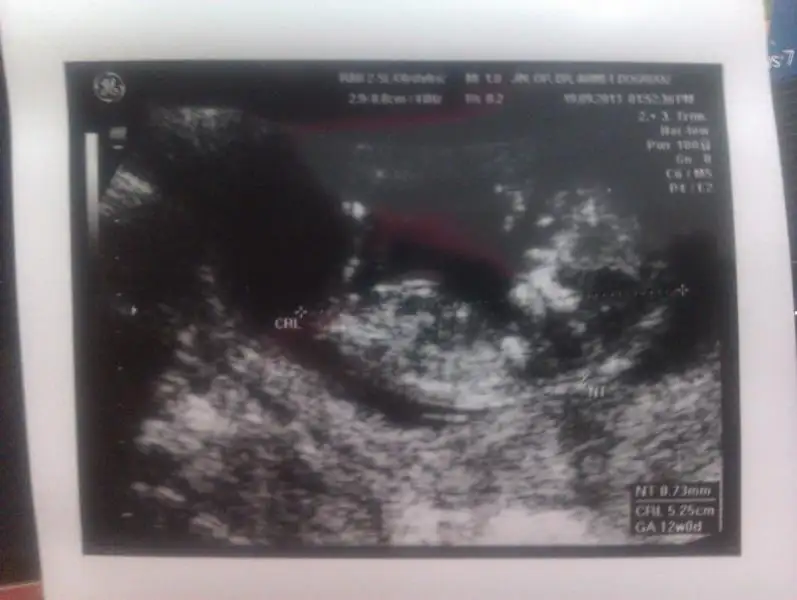

Benimkine de bakar mısınız? :)) Heyecanlandım şimdiEki Görüntüle 813587 Eki Görüntüle 813589

büyük ihtimal erkek gibi geldi bana